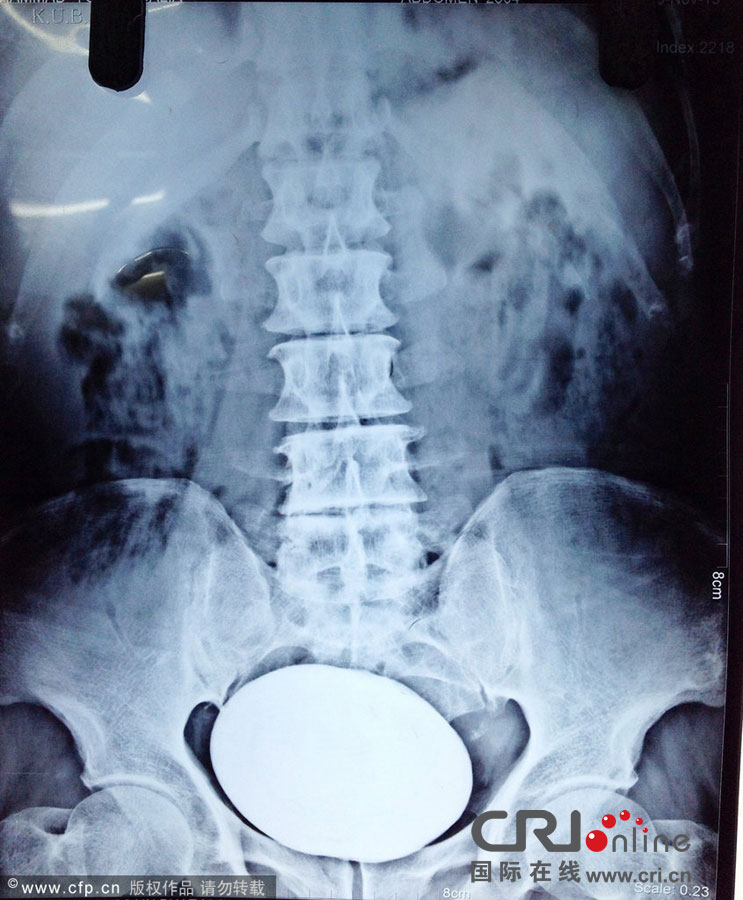

세계 최대 크기의 방광 결석